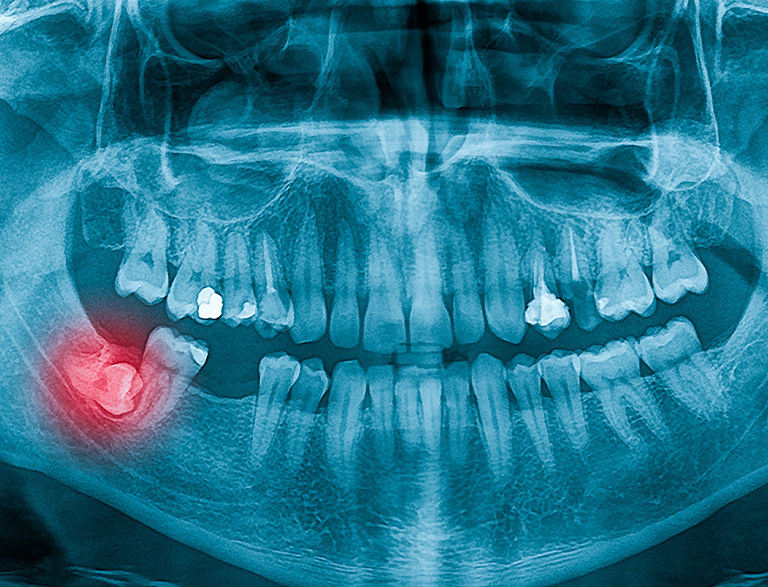

- Impacted or problematic wisdom teeth: Wisdom teeth often don’t have enough room to emerge properly, often leading to discomfort, infection, and misalignment. Removal can help prevent these issues and protect your smile.

Wisdom Teeth Removal: Protect Your Oral Health

Wisdom teeth often need removal if they’re impacted or causing discomfort, infection, or misalignment. No matter the cause, we’ll guide you through the process with anesthesia options to help keep you comfortable.

Our skilled dental team uses modern AI-driven technology to plan and perform your extraction. Depending on your needs, we offer local or sedation anesthesia to keep you comfortable.